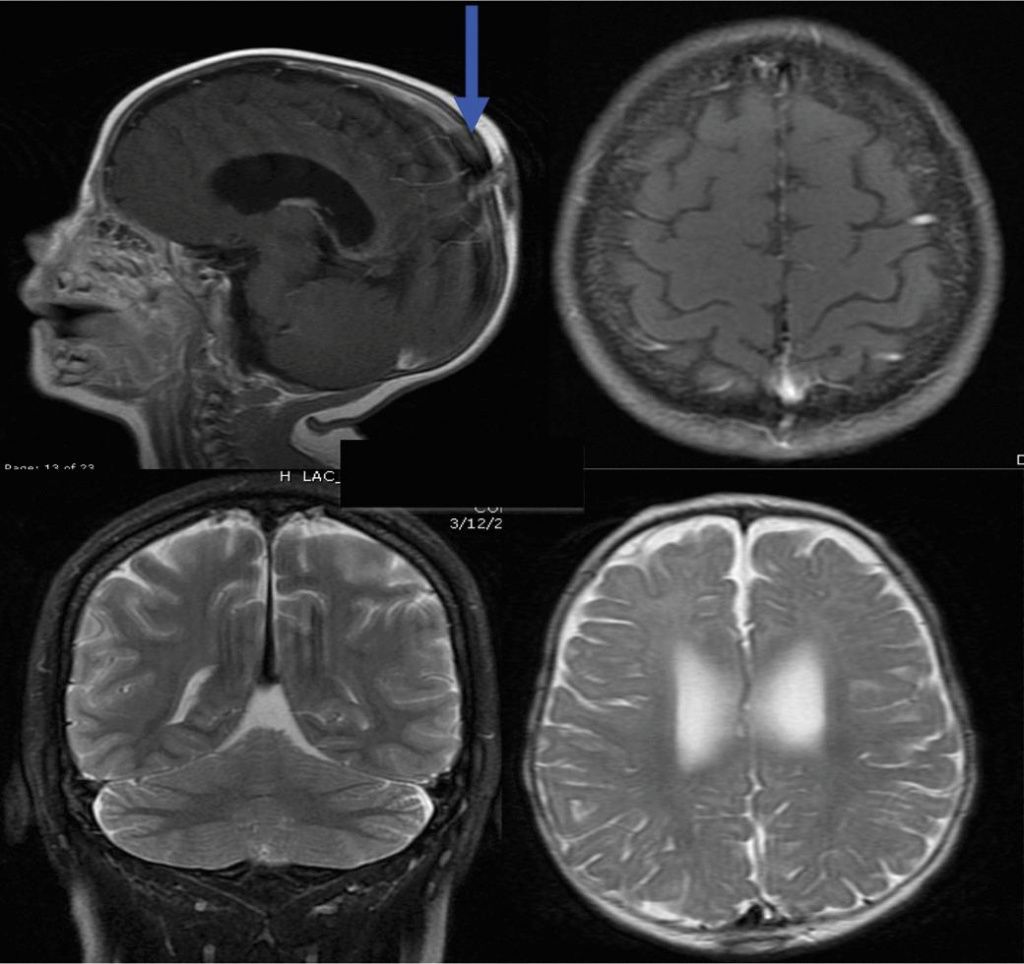

МРТ головного мозга: показания и результаты

Раздел: Визуальный дайджест